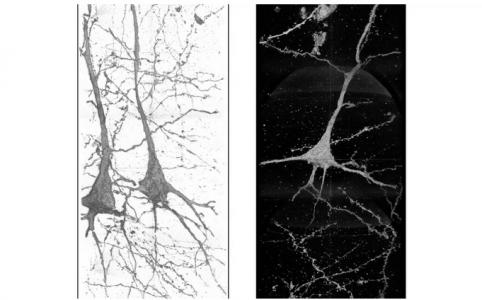

C’est l’objectif du Dr Ryuta Mizutani, professeur de biochimie appliquée à l'Université de Tokai au Japon, qui compare ici, avec son équipe, la structure du tissu cérébral de patients schizophrènes vs des témoins en bonne santé mentale, pour identifier des différences ou signatures de la maladie. Des techniques d’analyse 3D des tissus cérébraux, extrêmement rares dans le monde (synchrotron géré par l’ANL) ont permis ici à l’équipe de mener cet examen de 8 petits échantillons de tissu cérébral dont 4 issus de cerveaux sains et 4 de patients schizophrènes, tous prélevés post-mortem. Des images de ces tissus en 3D extrêmement précises ont ainsi été obtenues.

Capturer ces images en si haute résolution représente un défi, car les neurones imagés peuvent mesurer plusieurs centimètres de long. Le neurone est l'unité de travail de base du cerveau, une cellule du système nerveux qui transmet des informations à d'autres cellules pour contrôler les fonctions du corps. Le cerveau humain possède environ 100 milliards de ces neurones, de différentes tailles et formes. La technique permet de tracer chaque neurone sur plusieurs mm à travers l'échantillon. Ces images révèlent que :

- les structures de ces neurones sont différentes et uniques chez chaque patient schizophrène, ce qui suggère que la maladie est associée à ces différences structurelles ;

- car les images de neurones sains de différents donneurs sont relativement similaires, tandis que les neurones de patients schizophrènes sont de structures variables, à la fois par rapport aux cerveaux sains et entre eux.